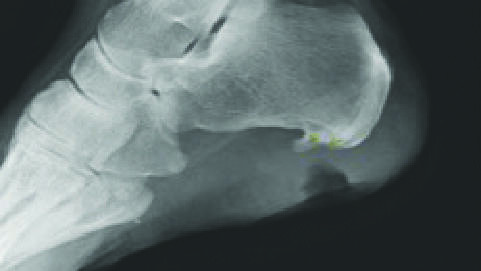

Comparing Medical vs. Surgical Management of Osteomyelitis in the Diabetic Foot

A poster to be presented at the Symposium on Advanced Wound Care (SAWC) Fall next week in Las Vegas evaluated the clinical outcomes in the published literature on medical and surgical management of diabetic foot osteomyelitis (DFO).1